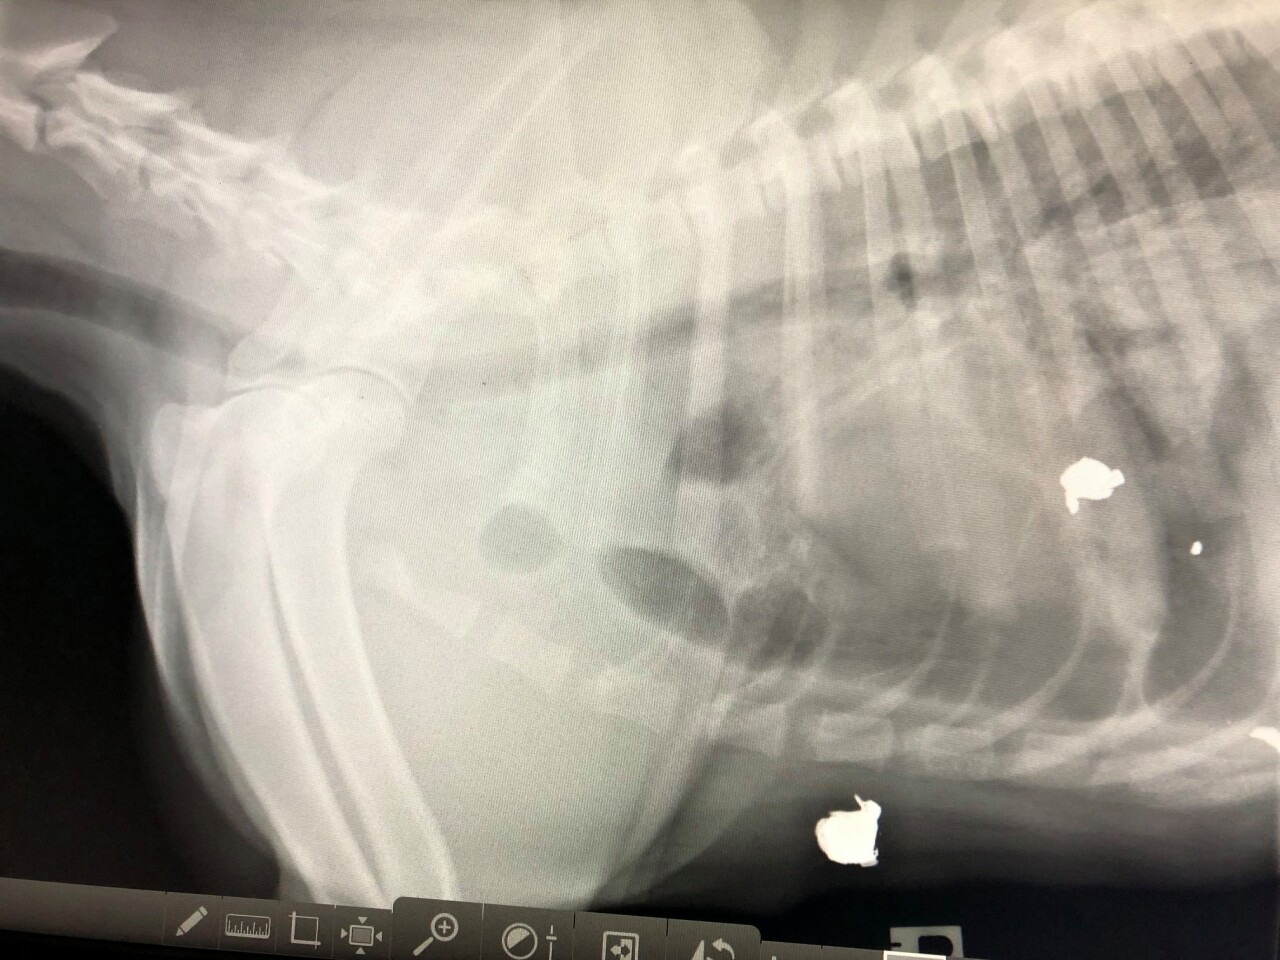

So far, they say they raised enough to cover Buster’s initial bills, but he is scheduled for surgery to amputate a toe damaged by one of the bullets. The shelter also shared images of x-rays that show bullets still embedded in Buster.